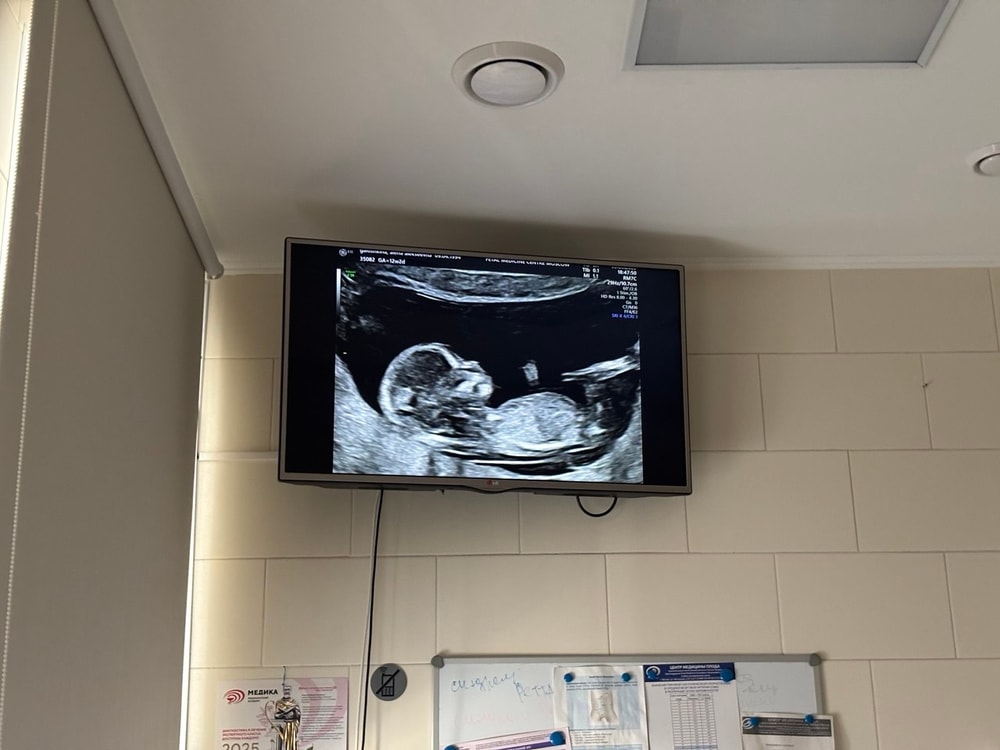

Из самого важного - сходили на 1 скрининг в хороший центр. Врач все внимательно посмотрела, муж рядом сидел, тоже смотрел )

Вот такая заечка у нас растет :) сказали, что опережает ровно на неделю - поэтому ПДР сдвинули на 8 февраля